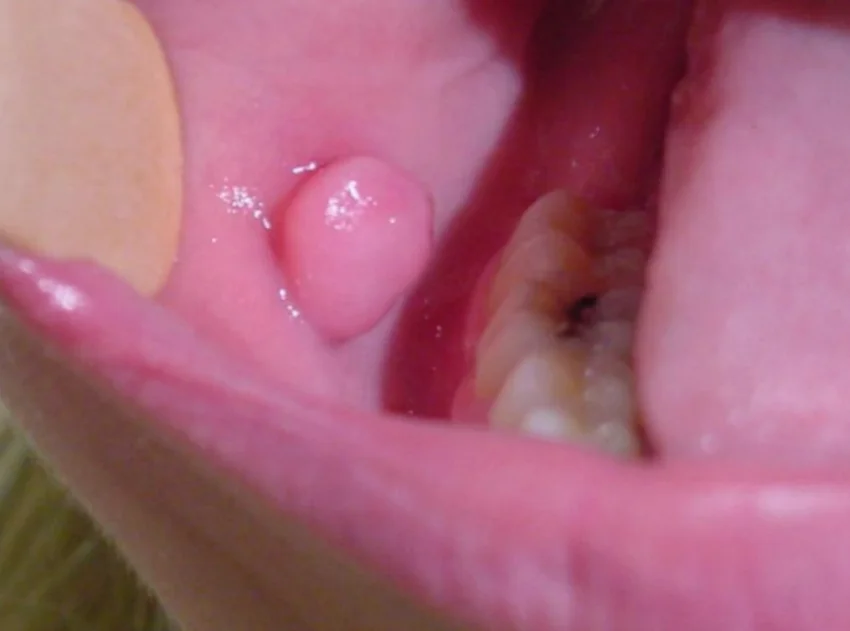

- Fibroma / irritációs fibroma (fokális fibrosus hyperplasia) – a leggyakoribb „jóindulatú csomó”, többnyire krónikus mechanikai irritáció (harapás, fogszél) talaján.

Szájüreg, garat vagy gége beningus tumor eltávolítása

Szájüregi fibroma